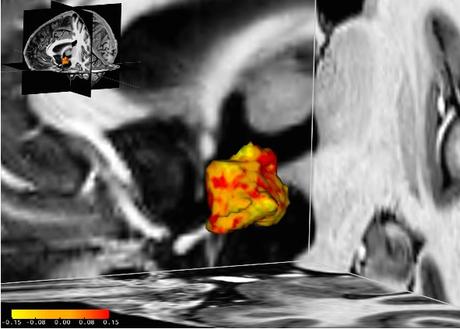

Chez ces patientes dépressives, les zones de l'hypothalamus (en rouge sur visuel) sont plus développées que chez leurs homologues en bonne santé. Les chercheurs suggèrent que cette « hypertrophie » pouvait résulter soit d’une prédisposition, soit de l’exposition à des facteurs de stress environnementaux. On savait déjà sait que les personnes plus prédisposées à la dépression présentent un dérèglement du système de réponse au stress endogène ou axe hypothalamo-hypophyso-surrénalien (axe HPA), qui est normalement déclenché en cas de situation stressante. Cette réponse augmente les niveaux de cortisol, fournissant au corps plus d'énergie lorsqu'il est confronté à une menace ou à un défi. Une fois la situation difficile passée, plusieurs mécanismes de contrôle de l'axe HPA garantissent normalement un retour à l'équilibre du système.

Un dysfonctionnement du mécanisme de rétroaction de l’axe HPA : chez les personnes souffrant d'un trouble dépressif ou prédisposées à la dépression, ce n'est pas le cas. Le dysfonctionnement du mécanisme de rétroaction entraîne une réponse au stress fonctionnant à plein régime, même en l'absence de stress apparent. Jusqu'à présent, la raison sous-jacente de ce système de réponse au stress hyperactif et le rôle de l'hypothalamus dans ce processus restaient mal connus. L’étude menée à l'aide d'un scanner IRM haute résolution auprès de 84 participants, révèle que :

- l'hypothalamus gauche est en moyenne de 5% supérieur chez les patients dépressifs vs leurs homologues en bonne santé ;

- cette constatation est effectuée également chez des patients souffrant de trouble bipolaire ;

- enfin, chez un groupe de participants souffrant de dépression, plus la dépression est sévère, plus l'hypothalamus est élargi ;